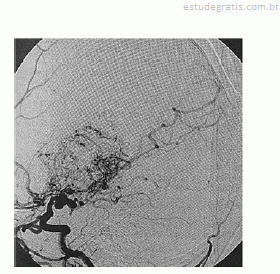

Paciente de 16 anos de idade, do sexo feminino, de asscendência japonesa, com deficits neurológicos progressivos iniciados ainda na infância, tem diagnóstico prévio de anemia falciforme. Realizou exame complementar de imagem do encéfalo, apresentado na reprodução acima. Há suspeita de doença de Moyamoya.

Em relação ao caso descrito, julgue os itens a seguir.

A inflamação da camada elástica interna faz parte da fisiopatologia.Comentários